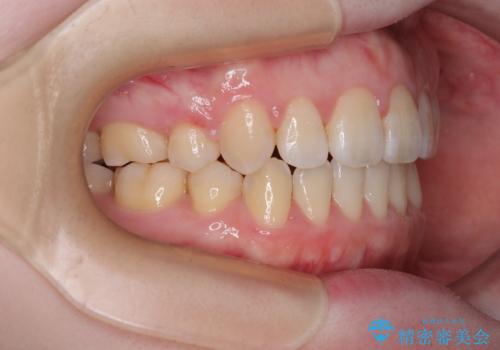

口元の突出感が改善されてことで、下唇に引っかかっていた上顎前歯も気にならなくなりました。

強い舌の突出癖により、上下前歯が前方に飛び出しており、特に上顎前歯は下顎よりも更に前方に位置している状態でした。